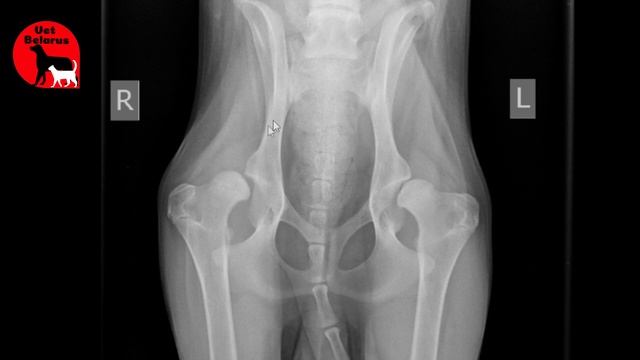

Дисплазии задних лапах